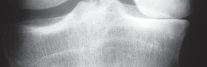

التصوير الطبي ضروري لتأكيد التشخيص وتحديد مدى تلف المفصل:

-

الأشعة السينية العادية (Plain Radiographs):

- منظر شروق الشمس (Sunrise/Patellofemoral): لتقييم المفصل الرضفي الفخذي.

- الأشعة السينية الطويلة للطرف السفلي بالكامل (Full-length standing radiographs): من الورك إلى الكاحل، وهي مفيدة جدًا، خاصة إذا تم استخدام تقنيات الملاحة الحاسوبية. تُظهر هذه الأشعة المحاذاة الكلية للطرف السفلي.